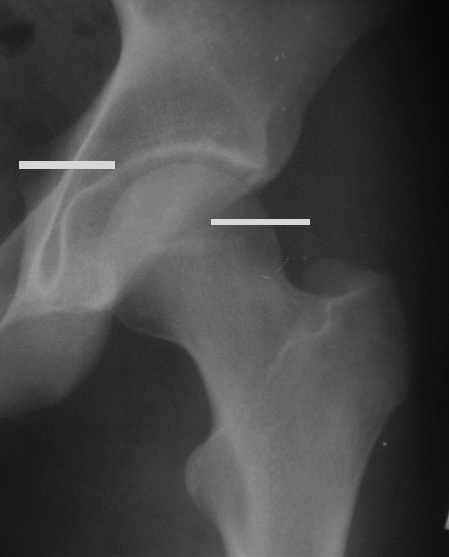

Уважаемые коллеги! Заканчивая обследование больного с переломо-вывихом бедра сделал ему обычные R-томограммы. Кажется удалось "поймать" и отломок и донорское место. Мои выводы - в скиаграмме. Считаю, что это передне-нижний фрагмент головки, образовавшийся вследствии отрывного перелома. На томограммах отломок обозначаю длинной стрелкой, а место откуда он оторвался - более короткой. Учитывая тот факт, что его размеры по КТ 25 х 15 мм считаю, что его фиксация на место необходима для профилактики артроза, что при 16-ти летнем возрасте пациента важно в плане максимального отодвигания эндопротезирования. Планирую оперировать его 24.05.05 г. Результаты представлю.

Несколько соображений к "картинкам". На прямом снимке и КТ-томограммах все типичные линии вертлужной впадины: крыша, передняя стенка, задняя стенка - сохранены. На КТ-сканах 6 и 7 появляется фрагментация головки. С учетом R-томограмм отломок расположен спереди-снизу, а не сзади-сверху от сустава, как написано в описании КТ.